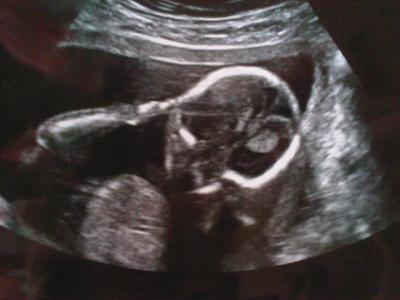

mein süsser bauchzwerg :-)

hier mal ein Us-bildchen vom Kh von gestern. die Fä fand das soo süss wie das kleine sich "die ohren zu hielt" deshalb gab sie und ein Us-Bildchen mit :-) lebe grüsse und einen schnönen sonntag noch